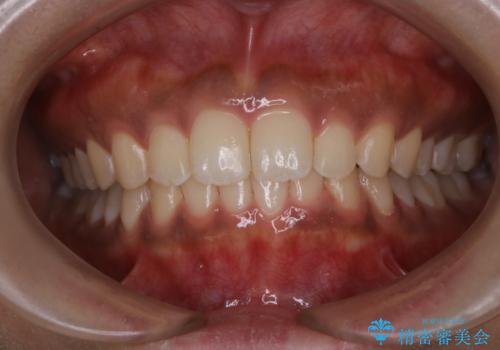

タバコのステインを徹底的に除去

- タバコによるステインを綺麗にしたいとのことでした。

PMTC60分コースを行いました。

タバコに含まれているものの中で、タールというものが歯の黄ばみの原因です。その黄ばみなどを、無理に落とそうとしたりすると歯の表面に傷がついてしまったり余計に汚れがつきやすい状態になることがあります。

PMTCでは、歯の表面の凸凹にミネラルを補給して、ツルツルの表面に仕上げます。定期的にPMTCを行うことにより、歯質の強化になり着色がつきにくい状態になります。